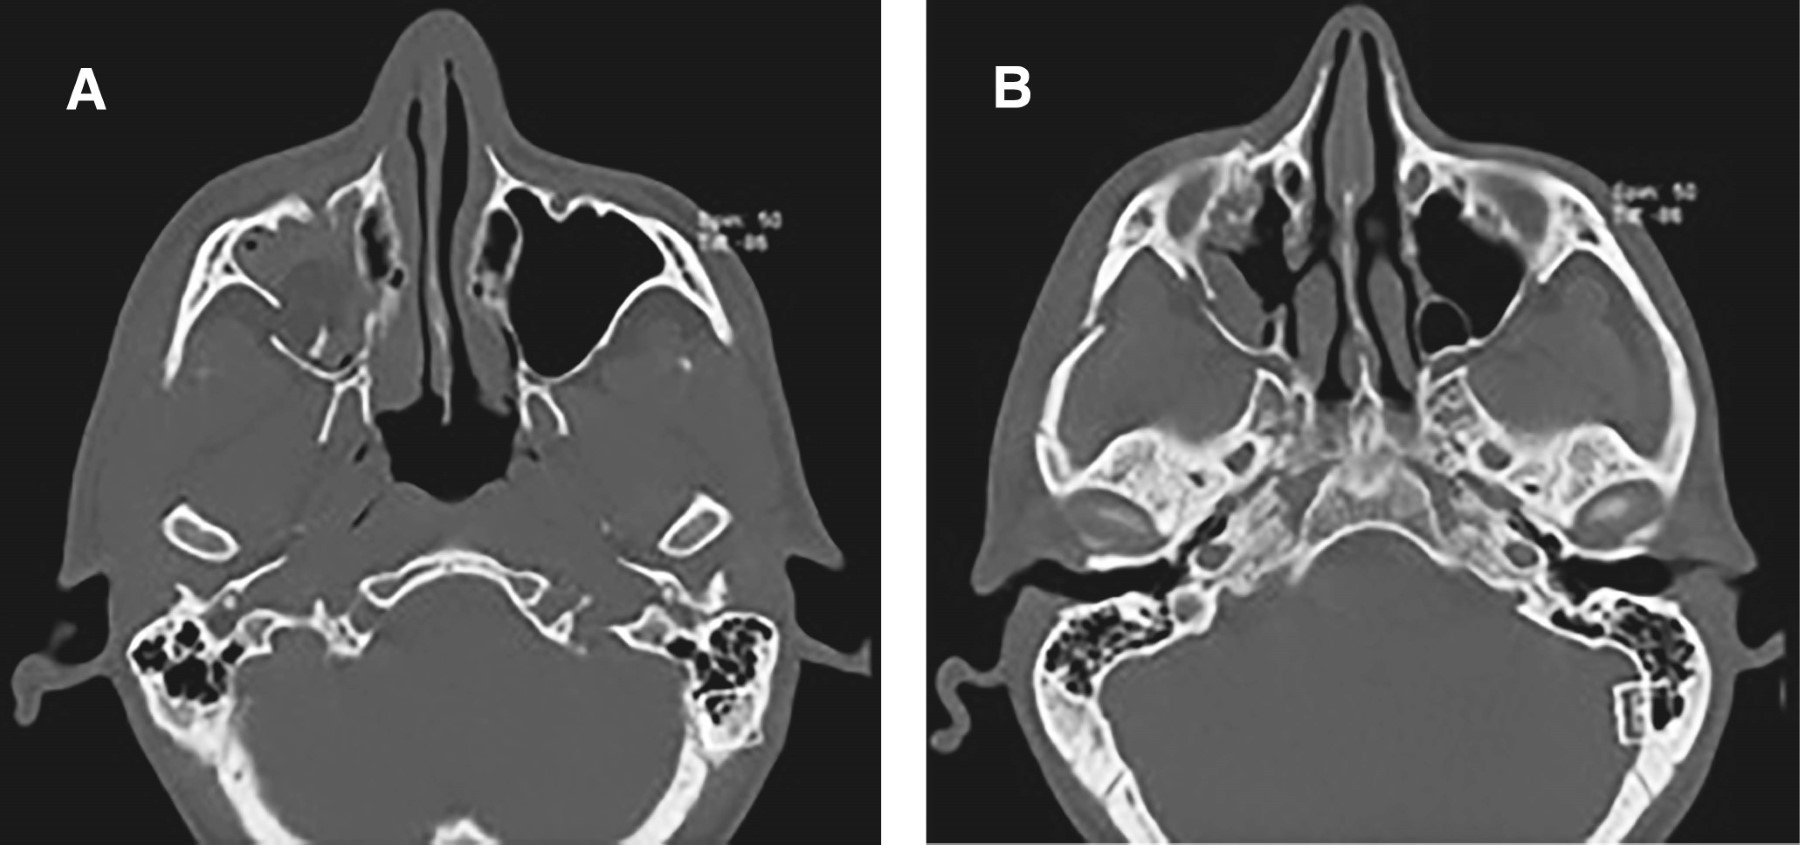

Se realizó tomografía computarizada (TAC) maxilofacial con reconstrucción tridimensional (3D) en las etapas preoperatoria y postoperatoria (a los seis meses de seguimiento). El electrocardiograma evidenció ritmo sinusal. Los exámenes de laboratorio se encontraron dentro de los rangos fisiológicos de normalidad (Figuras 4, 5 y 6).

Fractura orbitocigomático maxilar derecha consolidada. Se consideró como fractura consolidada utilizando los criterios clínicos que presentaba el paciente como ausencia de dolor, inmovilidad de los fragmentos fracturados y buen control de hemostasia. Además, fue relevante la cantidad de días transcurridos desde origen del trauma.

En pabellón central bajo anestesia general, intubación nasotraqueal en narina izquierda. Antisepsia de tejido mucocutáneo facial con povidona yodada 10%, conformación de campos estériles. Demarcación de incisión e infiltración anestésica con lidocaína al 2%, aplicación de un tubo subcutáneo en parpado superior derecho y dos tubos en fondo de vestíbulo maxilar derecho. Abordaje blefaroplastia derecha. Incisión con bisturí frío sobre herida. Diéresis roma y luego en pilar frontocigomático derecho se observa el rasgo de fractura sin desplazamiento. Se realiza osteotomía con cincel para separar fragmentos fracturados. Se posiciona placa Synthes sistema 1.5 de 5 orificios, perfil 0.5 mm. Se tracciona malar en sentido cefálico desde cabo inferior de fractura. Se realiza fresado y se posicionan 4 tornillos de 5 mm. Se confirma reducción de fractura esfeno cigomática.

Se realiza un abordaje de vestibulotomía derecha con electrobisturí en fondo de vestíbulo, decolado mucoperióstico hasta exposición ósea maxilar y cigomática. Se observa fractura de unión de ambos huesos con desplazamiento posterior. Se reduce cigoma. Se posiciona placa en L, ocho orificios y puente intermedio, placa synthes sistema 1.5, perfil 0.5 mm. Se posicionaron dos tornillos 6 mm y tres tornillos de 5 mm. Se confirma reducción de fracturas.

Mediante abordaje blefaroplastia, se accede a fosa temporal. Se desimpacta arco cigomático. Reducción de fractura manual mediante legra. Se evidencia buen contorno facial.

En el presente caso, la falta de reducción temprana generó consolidación en mala posición con limitación del campo visual hacia la derecha y hundimiento malar, acompañado de edema y equimosis periorbitaria. Hallazgos similares han sido descritos por Lu y colaboradores2 y Vahidi y su equipo.7

Kiemle Trindade y colaboradores10 reportaron fijación en tres zonas (sutura frontocigomática, borde infraorbitario y pilar cigomático maxilar) en 46% de los casos. Sin embargo, cuando la estabilidad se logra con 1 o 2 puntos, no es necesario un tercero.10 En este caso se obtuvo adecuada estabilidad con fijación en dos puntos: pilares frontocigomático y cigomático maxilar.

La selección de dichos puntos obedeció a los signos clínicos observados, concordantes con los criterios descritos por Schneider y colaboradores,11 donde la fijación en la sutura frontocigomática permite recuperar la proyección lateral del malar y en la cresta cigomático maxilar estabilizar la oclusión.